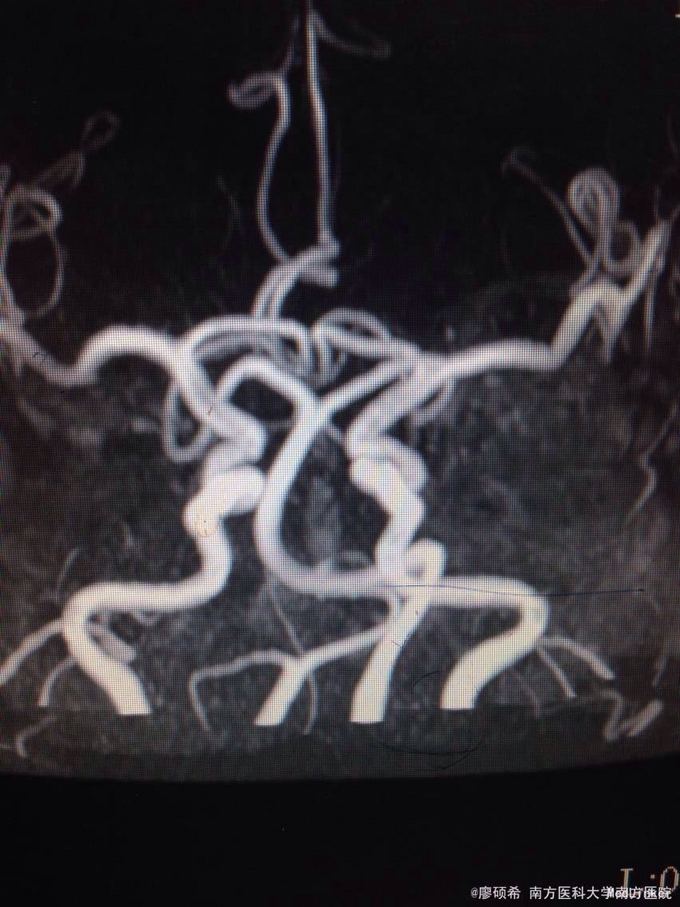

查体未见明显阳性体征。 颅脑MR示脑动脉硬化

基底动脉延长扩张症。予改善循环,营养神经等治疗。

患者颅脑MR影像科未报基底动脉延长扩张,上级医师自阅片子后决定给她下这个诊断。